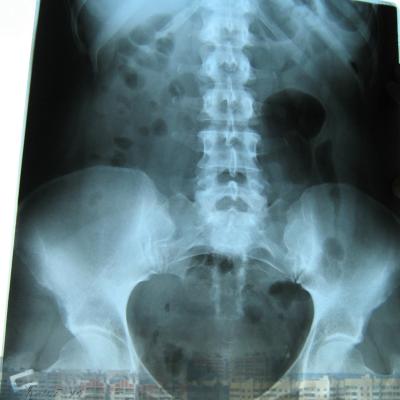

Была сделана операция 04.07.2012г по поводу нефропексии правой почки поясничной мышцей с помощью разреза. После операции болит правая сторона живота и в спине и в пояснице был затронут нерв, и до сих пор правая нога до колен не отходит спереди и сбоку. Через полтора месяца после операции образовался отек, пошло воспаление сзади на спине, потому что был затронут нерв. Сделала урографию через 4 месяца после операции. Если вас не затруднит, посмотрите пожалуйста снимки, правильно ли располагается мочеточник правый после операции. Скажите пожалуйста, посмотрев мои снимки, правильное ли расположение мочеточника и почему болит правая сторона живота все это время, и каким исследованием теперь после операции проверить что там творится в животе, что там затронуто? Все указывает на то что был затронут нерв, оперирующий врач говорит что не может быть такого, а я уже почти всю ногу правую не чувствую

Снимки прикрепляю

Абсолютно нормальное расположение почки и мочеточника . Но ведь и онемение нижней конечности с положением почки не связано. Есть такое понятие "футлярный синдром"- после вынужденного положения конечности. Проконсультируйтесь с неврологом.